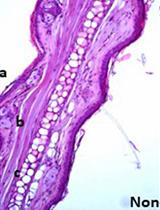

Figure 1. Representative Model of Intubating Platform